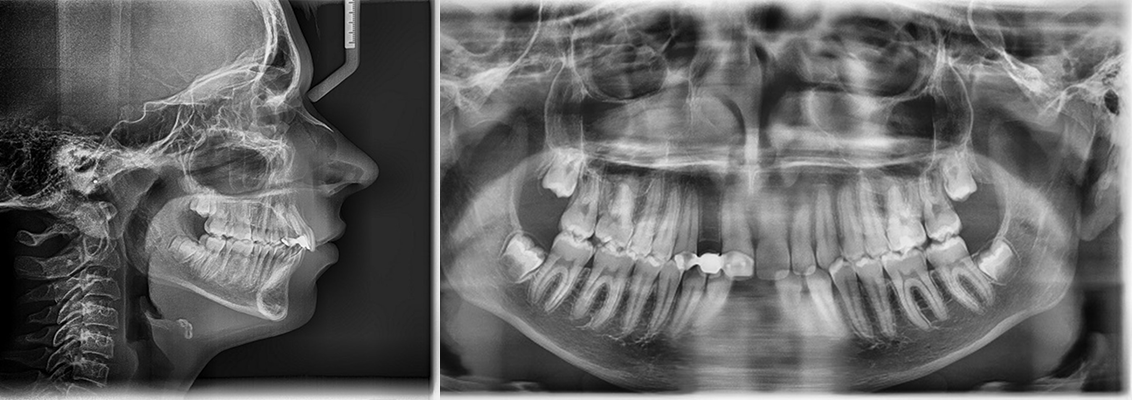

Age: 12 years

Main complaint: Aesthetic concerns and functional difficulties

Skeletal Class II due to mandibular retrognathia, proclination of maxillary incisors, narrow arch creating a V-shaped arch, agenesis of 12, 31, 41, hyperdivergent facial pattern, moderate deep bite (2 mm), increased overjet (9 mm), asymmetric canine and molar Class II due to mandibular deviation to the left, maxillary midline deviation related to agenesis of 12, distal rotation of 35 and 45, and pronounced lower curve of Spee.

Stimulate mandibular growth, reduce overjet, correct Class II relationships, level the curve of Spee, manage space opening for agenesis of 12, 31, and 41, recenter midlines, improve oral function.

A monobloc appliance was prescribed to stimulate mandibular growth.

After 6 months:

Overjet reduced from 9 mm → 4 mm

Clear improvement in labial competence, nasal breathing, and tongue function.